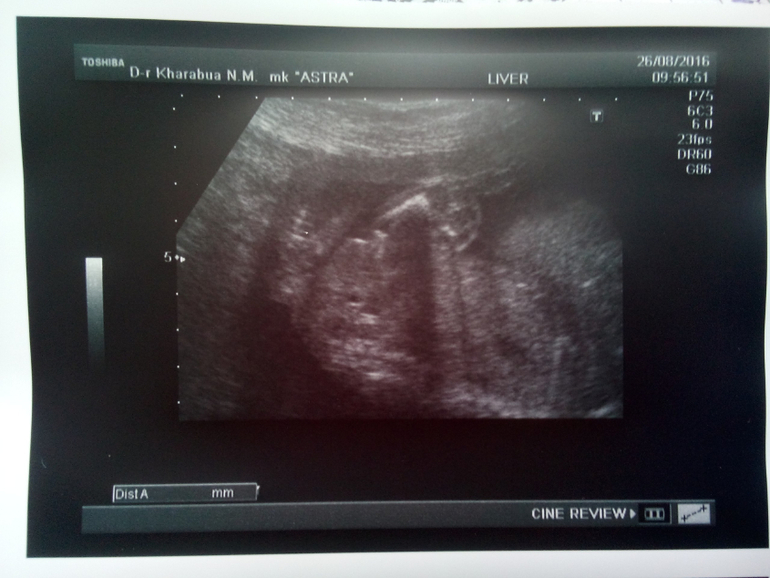

Все у нас хорошо. Ребеночек срокам соответствует. Здоров, активен. Шейка в норме, тонуса нет. Плацента высоко по передней стенке. В общем вообще все отлично.

Ну и интрига дня, которую я еще до вердикта врача раскрыла: у нас будет МАЛЬЧИК - сыночек и братишка для Сонечки) УРА!!

Ну и хотелось бы показать наше "достоинство" на фото. Я лично не сильно рассмотрела, но врач убедила, что девочки там быть даже не может. И писюн видно и мошонку, а так были бы явные "пирожочные" половые губы.